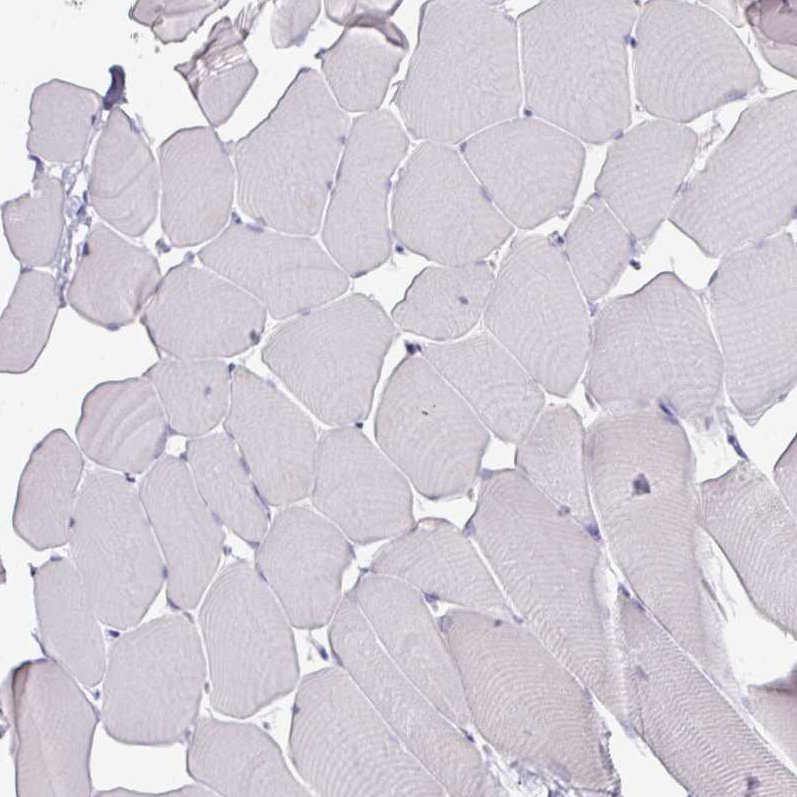

Immunohistochemistry analysis in human testis and skeletal muscle tissues using AMAb90541 antibody. Corresponding ATAD2 RNA-seq data are presented for the same tissues.